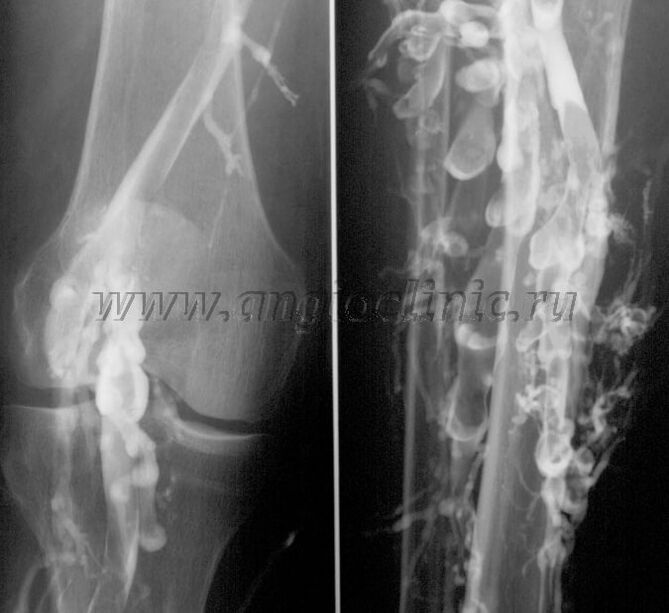

Contrast venography

Usually, an ultrasound scan is sufficient for a complete diagnosis of venous pathology, but in some cases it is necessary to study the state of the deep and superficial venous system, especially in the case of varicose veins and recurrence of secondary varicose veins.

Contrast X-ray examination is used to solve these problems.Saphenous veins are punctured and contrast is injected.The movement of the contrast is observed on the monitor of the X-ray machine and all necessary tests and projections are performed.Currently, venography is used very rarely for varicose veins.